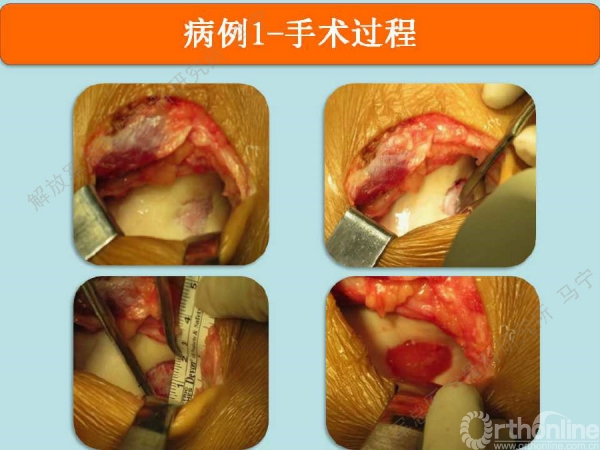

病例1

患者右膝疼痛6年,无绞锁,特别是蹲起困难,于2008年住我院,接受关节镜手术,发现股骨滑车局部软骨缺损。

术后8个月修复区的软骨厚度恢复理想,软骨下骨水肿信号不明显。术后16个月复查修复区的软骨没有太明显的变化。